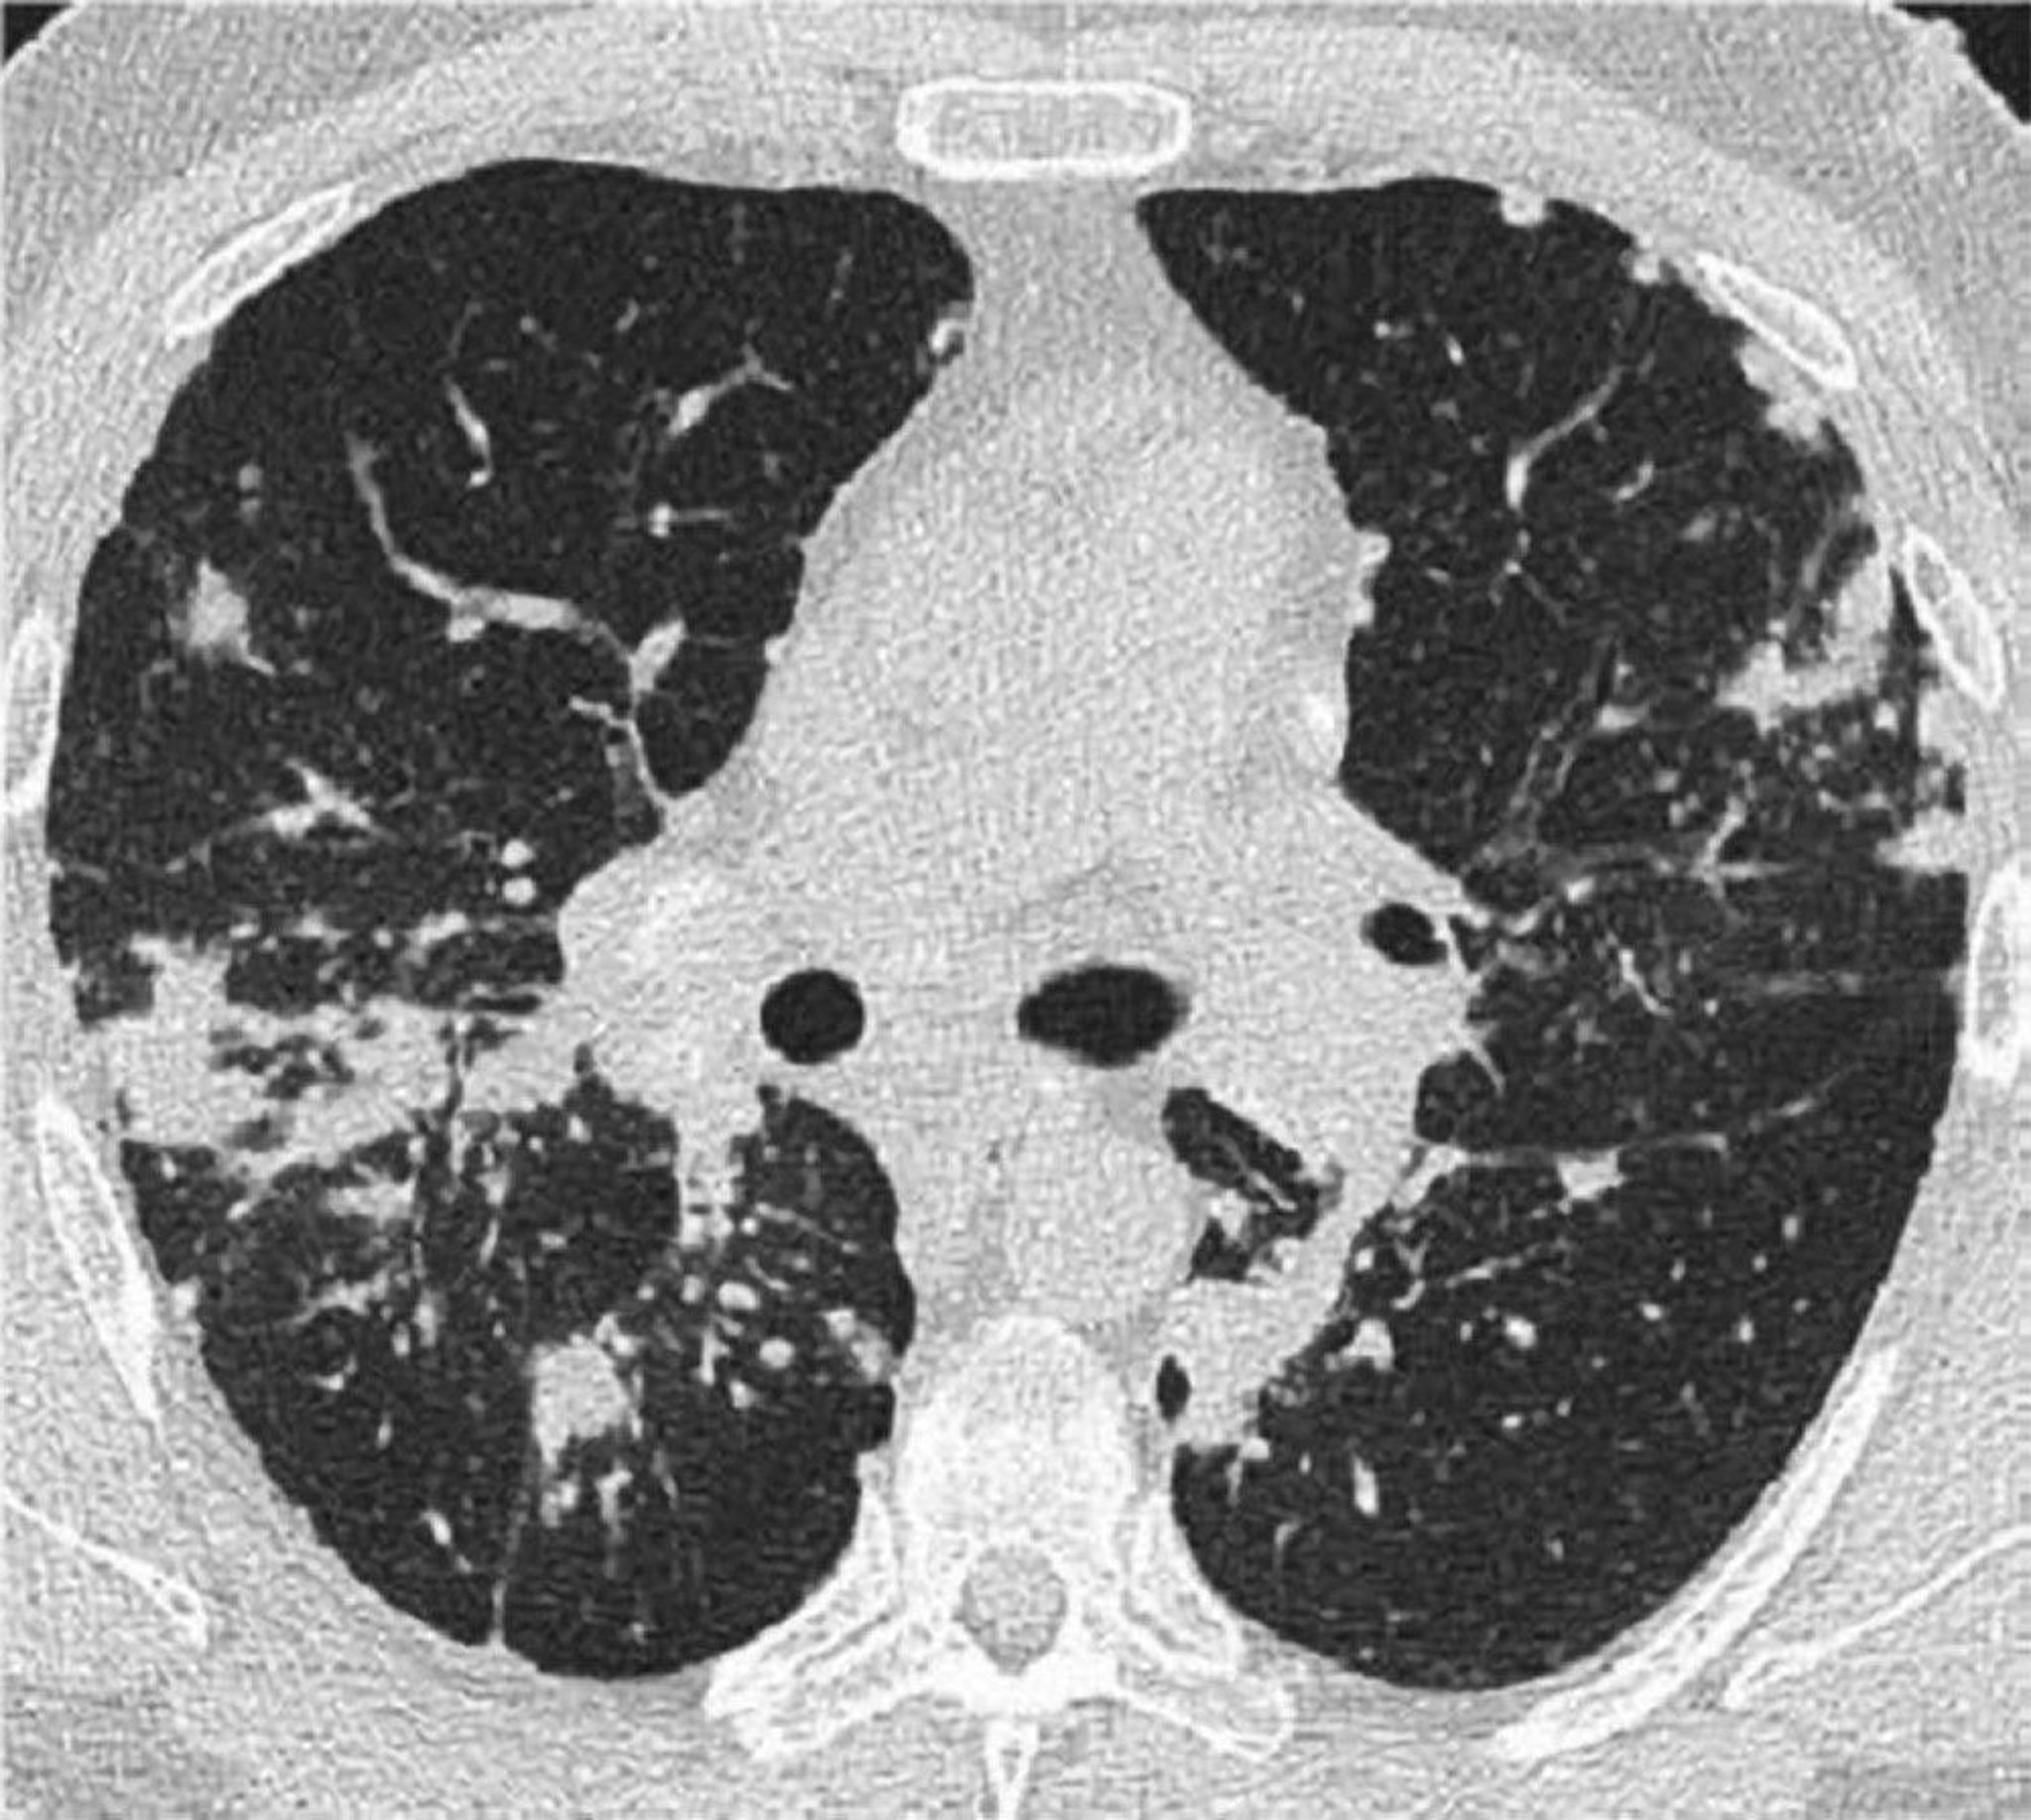

肺サルコイドーシスにおける胸部CT

この肺サルコイドーシス患者の胸部高分解能CT画像では,気管支血管束の肥厚と小葉間隔壁の数珠状変化が認められる。

Image courtesy of Birendra P.Sah, MD, FCCP.